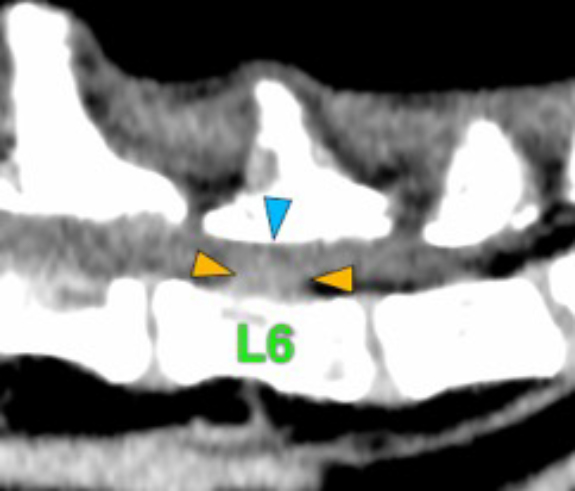

The osteolytic lesions have soft tissue attenuation that shows moderate and slightly heterogeneous post-contrast enhancement. In some of the vertebrae, the lesions cause lysis of the cortex and extend into the vertebral canal (orange arrows) causing variable degree of compression of the spinal cord and cauda equina (blue arrows). At the level of the vertebral bodies of T7, T8, T9 and T12 the lesions extend into the ventral and central aspect of the vertebral canal causing a mild compression of the spinal cord. At the level of T13, L1, L4 and L5 the lesions extend into the ventral and central aspect of the vertebral canal, causing moderate compression of the spinal cord. At the vertebral body of L6 the lesion extends into the ventral and central aspect of the vertebral canal, at the mid-aspect of L6, occupying approx. 90% of the diameter of the vertebral canal causing a severe compression of the cauda equina. At the level of L7, the lesion extends into the ventral and both lateral aspects of the vertebral canal, causing severe compression of the cauda equina.